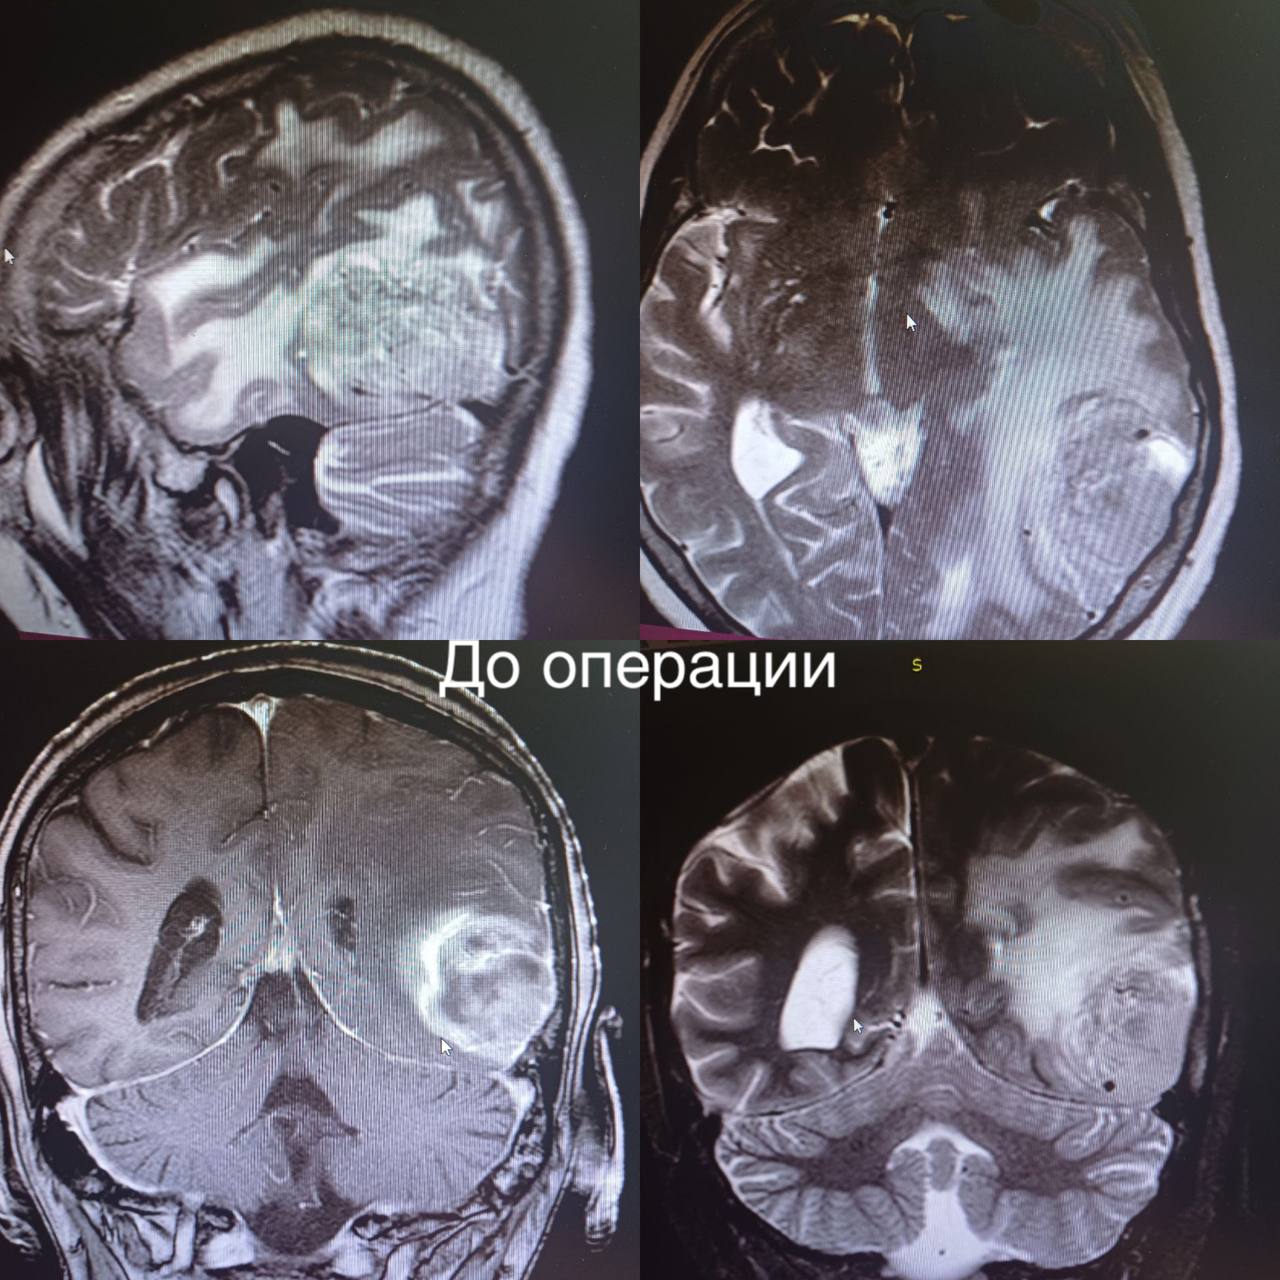

Пирамидная симптоматика в неврологии: ключевые аспекты